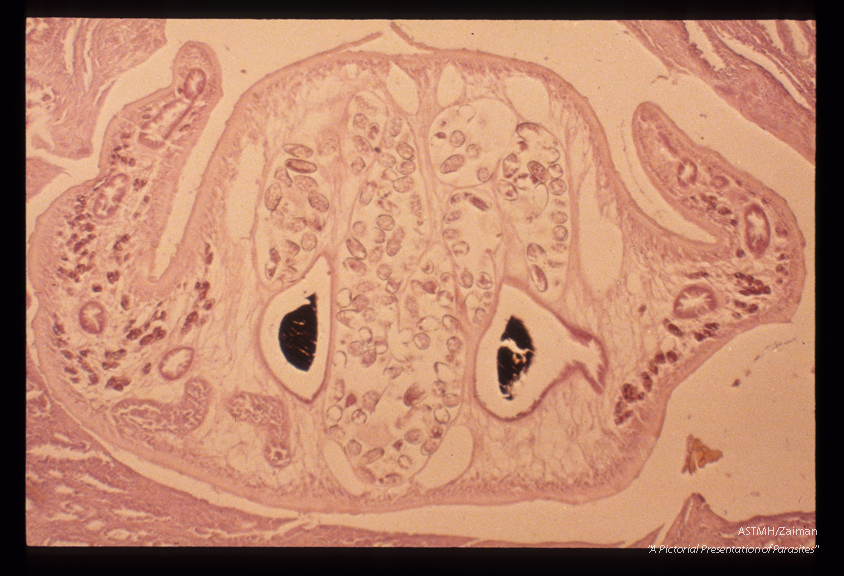

Liver, Cuticular spines, a complicated gut pattern due to multiple branching caeca and characteristic ova differentiate Fasciola from Clonorchis in tissue.

Description: Liver, Cuticular spines, a complicated gut pattern due to multiple branching caeca and characteristic ova differentiate Fasciola from Clonorchis in tissue.